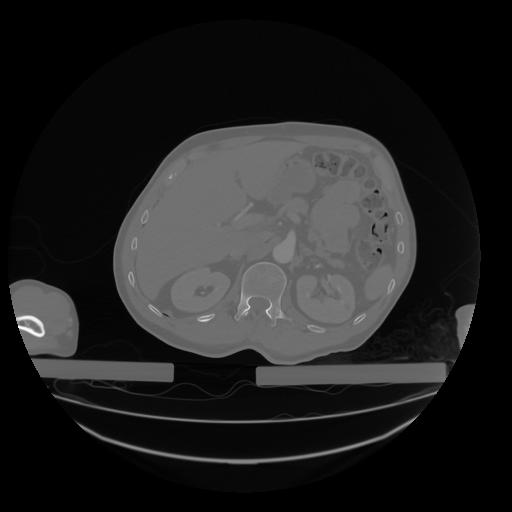

28 CUERPO,CE,Vol,2.0,CUERPO,,